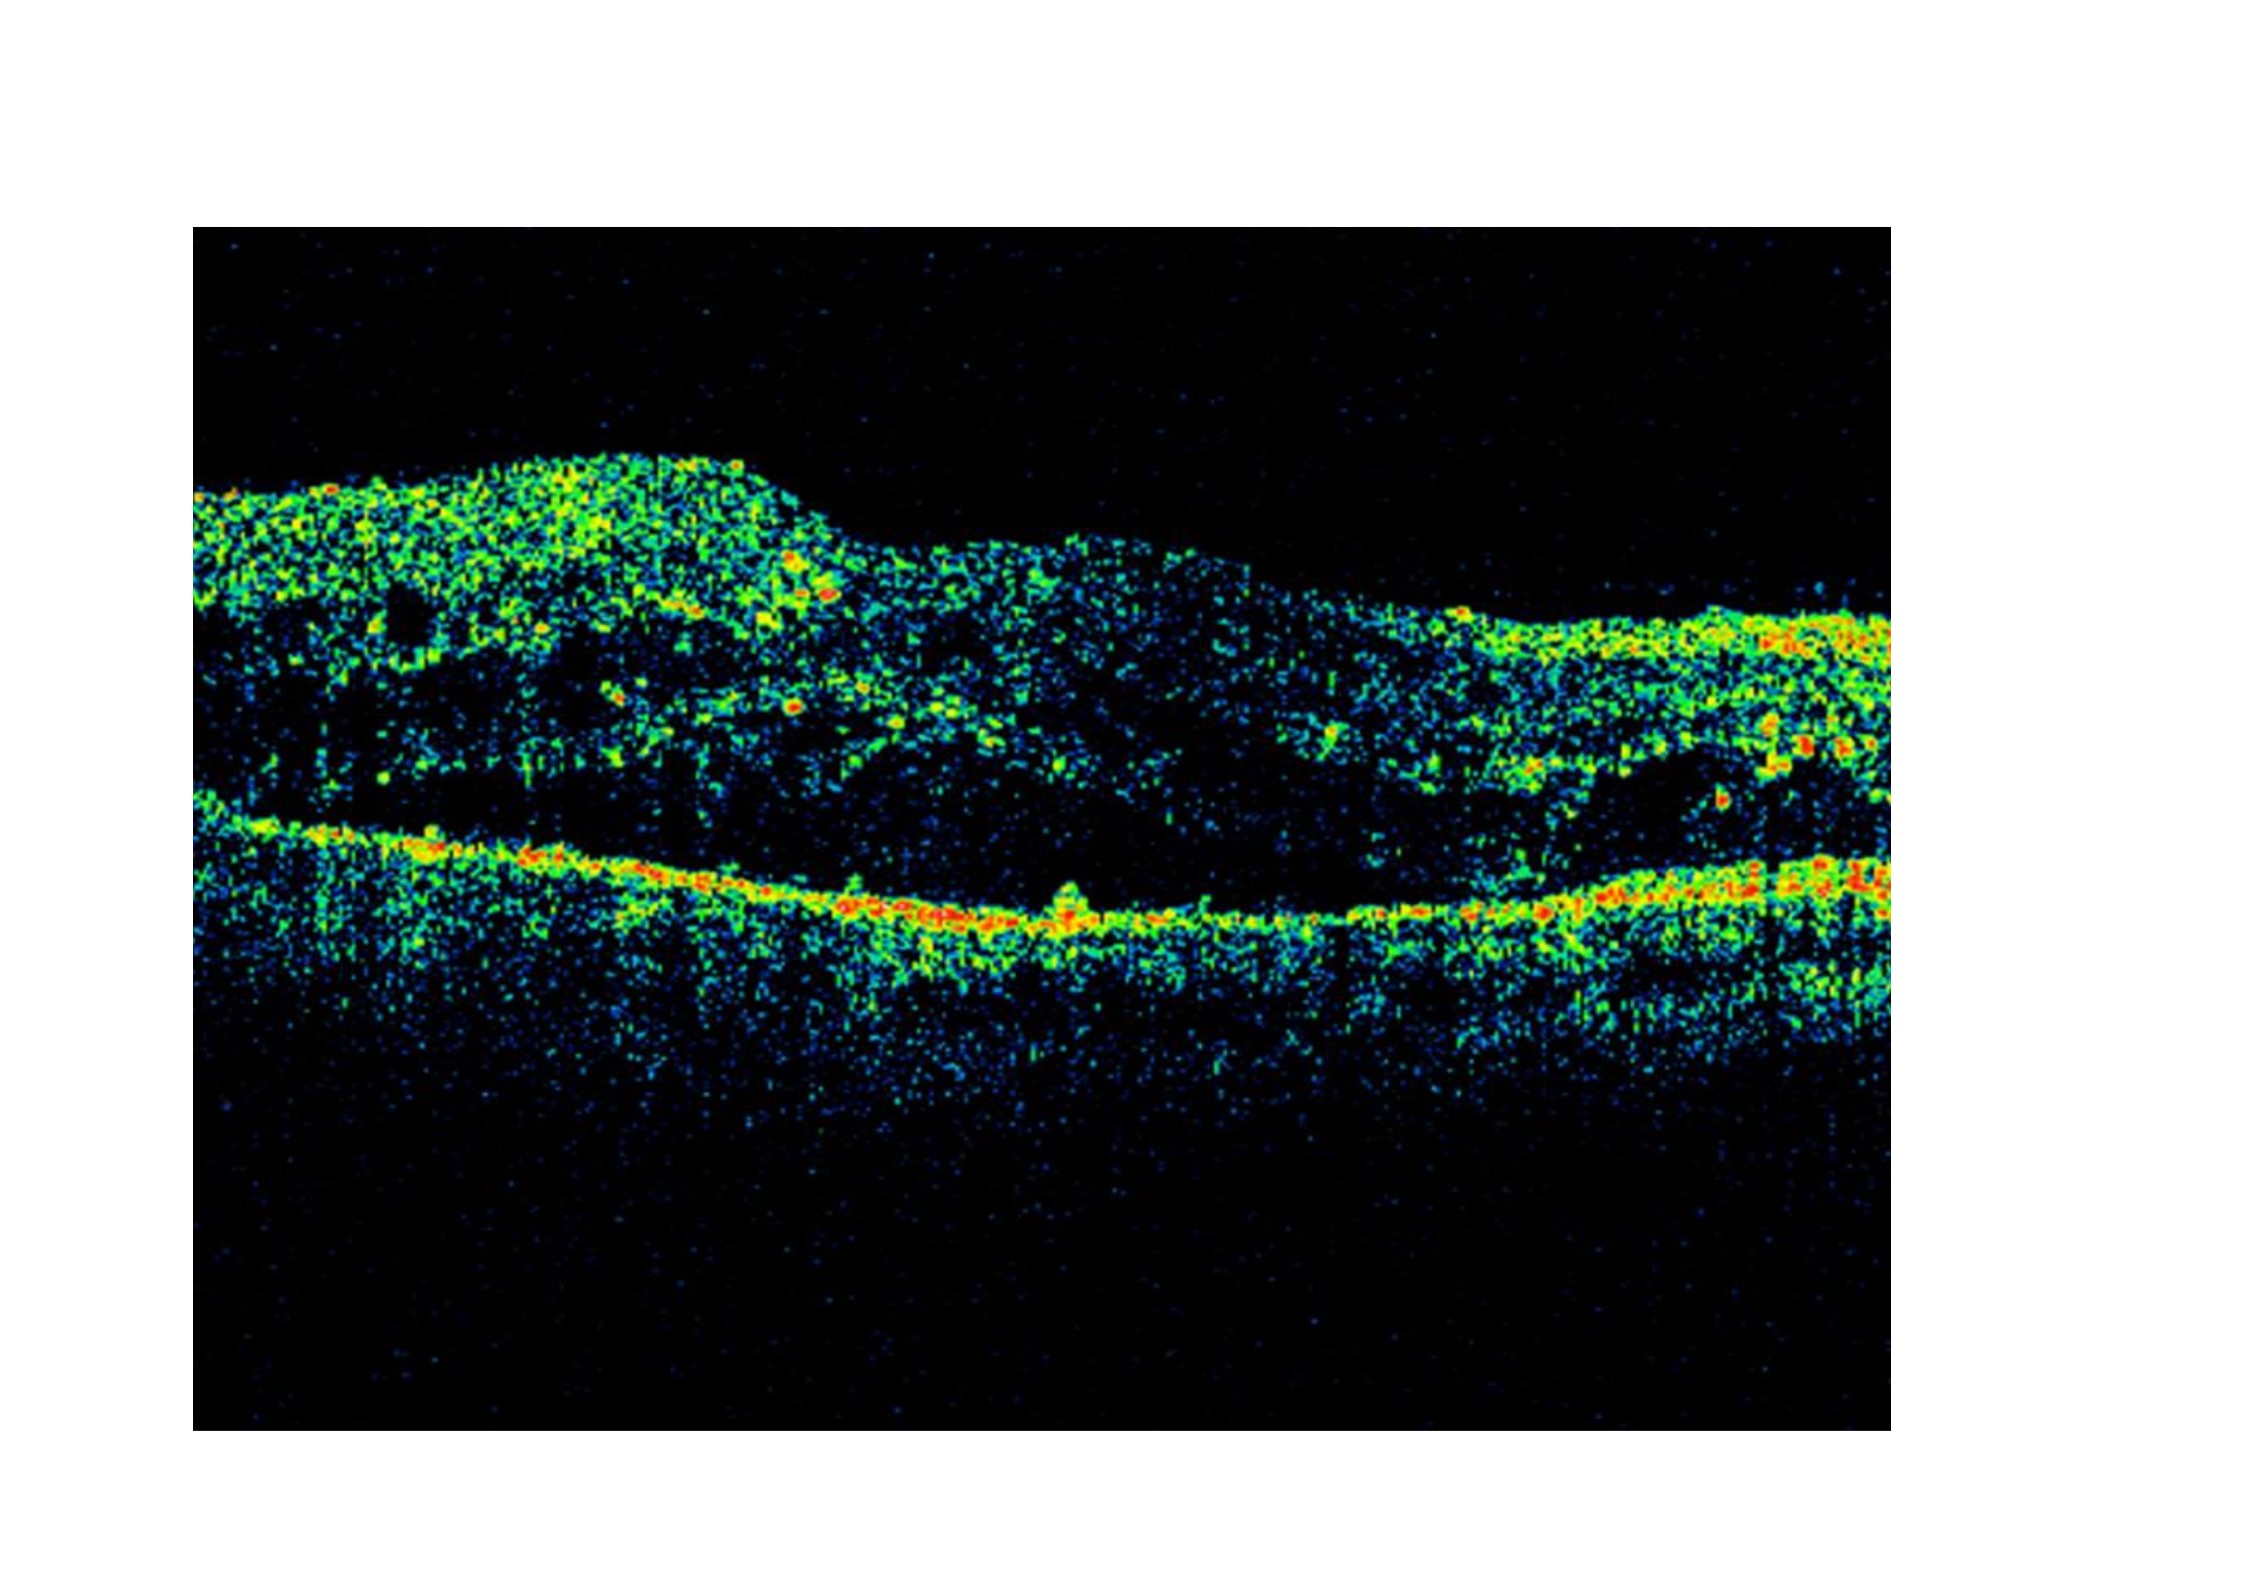

Las inyecciones las realizaron en jeringas distintas y en sitios separados, siendo seguidas de una paracentesis de cámara anterior. Todos los pacientes estaban afectados de edema macular diabético persistente que había sido tratado previamente con fotocoagulación láser y/ó inyecciones múltiples intravítreas de bevacizumab. La agudeza visual de los ojos tratados era en todos los casos de 20/50 o menor. La AV mejoró desde una media antes  del tratamiento de 0,82 (0,34) logMAR a 0,34 (0,26) log MAR 6 semanas después del tratamiento. El grosor macular central pasó de una media de 409 (74) micras a 314 (29) micras a los 6 meses del tratamiento. En ningún caso se encontró daño retiniano por toxicidad mediante electrorretinograma.

em 2_0000